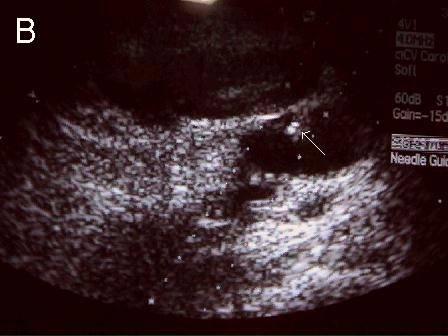

A 连接三联管及穿刺针准备 B 超声引导下注射针进入瘤腔底部(箭头处) C 经注射针注入盐水出现超声频闪现象; D 远端瘤腔内血栓逐渐形成; E 远端、近端瘤腔内血栓完全形成; F 术后足背动脉血流良好. 国内首家开展,例数最多,疗效肯定。此技术在全国推广应用。处于全国领先水平。 |